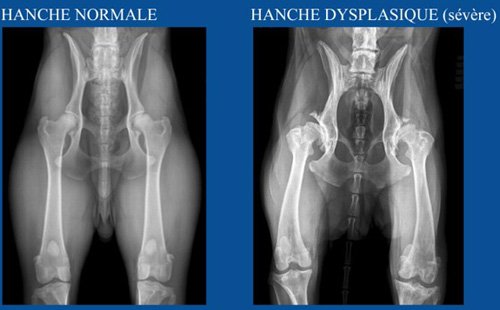

📊 Classification des hanches

5 Niveaux sont possibles : HD-A / HD-B / HD-C / HD-D / HD-E.

Ne sont considérés comme Hors Dysplasie que HD-A et HD-B.